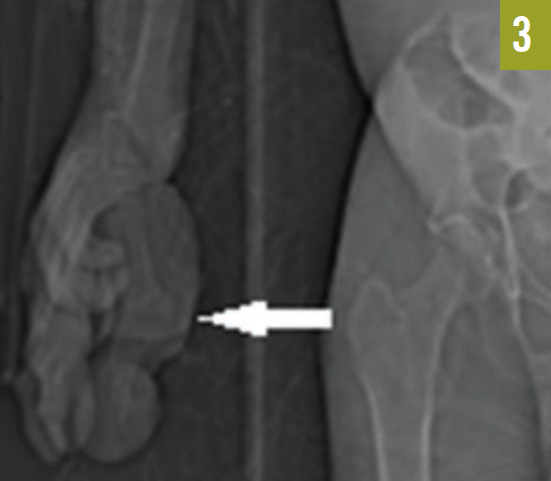

The patient had an established diagnosis of Proteus syndrome. On physical examination, he exhibited a cerebriform soft tissue nevus on the right palm (Figure 3), which is the result of a proliferation of collagenous tissue in the dermis and is highly specific for Proteus syndrome. Also noted was unilateral hypertrophy of his right hand and foot. A CT scan of the abdomen revealed massive splenomegaly, extending from the diaphragm to the pelvis (Figure 4).

Figure 3. A cerebriform soft tissue nevus was present on the right palm.